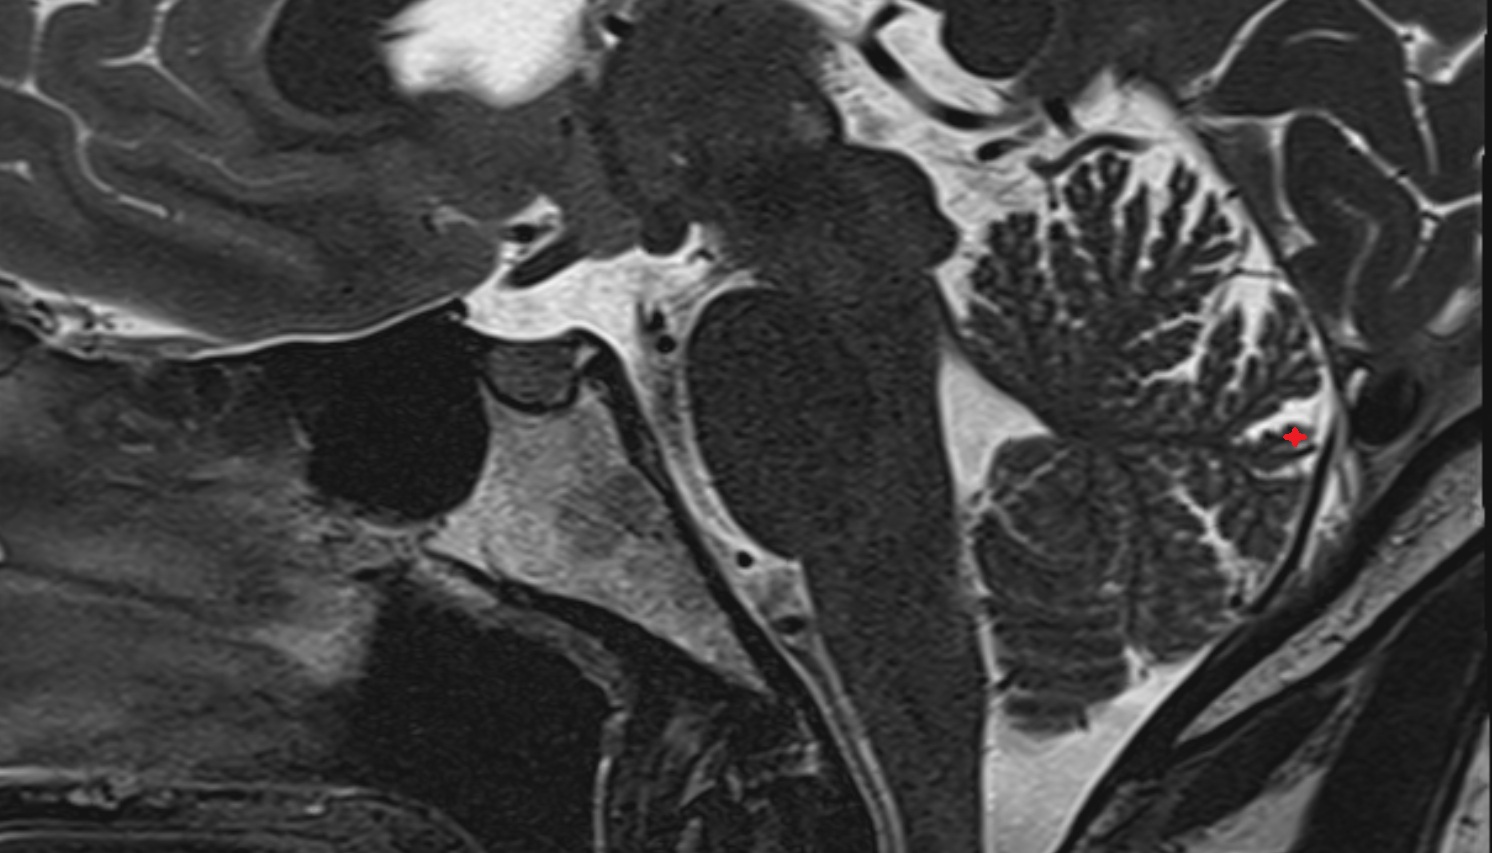

- Cerebellum

- Crus I of ansiform lobule of cerebellum

- Crus II of ansiform lobule of cerebellum

- Paramedian lobule (HVII) of cerebellum

- Simple lobule (HVI) of cerebellum

- Anterior quadrangular lobule (HV) of cerebellum

- Anterior quadrangular lobule (HlV) of cerebellum

- Biventral lobule (HVIII) of cerebellum

- Central lobule (II & III) of Cerebellum

- Culmen (IV, V) of Cerebellum

- Declive (VI) of Cerebellum

- Folium (VII) of Cerebellum

- Tuber of vermis (VII)

- Pyramid of vermis (VIII)

- Uvula of vermis (IX)

- Nodule of vermis (X)

- Cerebellar tonsil (H IX)